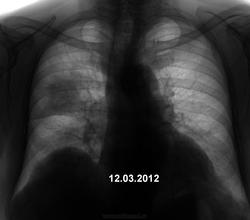

Пациент 77 лет обратился в п-ку с т.с. простудой, без яркой клиники. На флгр. поставили пневмонию(1-й снимок) и отправили на стацлеч.

Сделали и КТ, которая тоже подтвердила пневмонию (по заключению). Но меня терзают сомнения, а не торчат ли тут уши чего страшнее? Порекомендовал ч-з 1мес. контроль.

а не параканкрозного характера это? виден узел в правом легком.объём правого легкого уменьшен. нужна тг.

Не прохая динамика, но без томографии..., рисковано и очень...